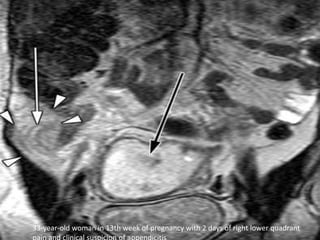

33-year-old woman in 13th week of pregnancy with 2 days of right lower quadrant

• Imaging modalities –Negative appendectomy rate: -Clinical diagnosis alone: 54% -Clinical, US & CT: 8%  1st Line:  US  2nd line:  CT (sensitivity 98%; specificity 98%)  MRI (sensitivity 100%)

33-year-old woman in13th week of pregnancy with 2 days of right lower quadrant